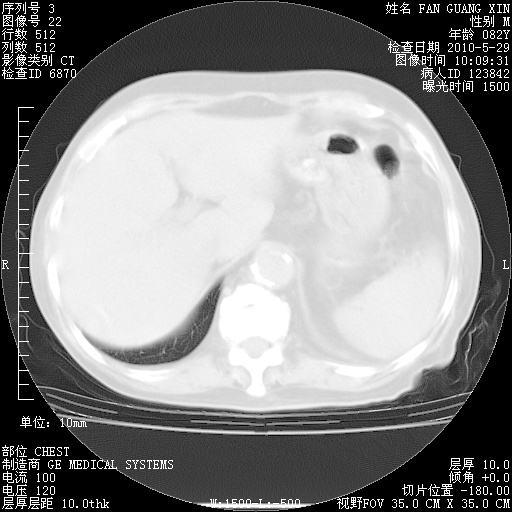

再治疗10天后的肺部CT

从白细胞总数和中性比例看好像合并感染。肺部纹理好像比上次多,支气管炎?其他感染?

阅读此次胸部CT,肺间质渗出性改变较入院时有吸收。目前从体温、白细胞、中性分叶明显增高,肯定存在细菌感染(发生医院感染哦,若无消化道及泌尿系统等感染的依据,肺部感染可能大)。若你院头孢哌酮舒巴坦钠耐药率较高,同意你的方案,若48小时体温仍高,可考虑使用碳青霉稀类抗菌药物,同时可予超声雾化、注意滴数时加大液体量。白蛋白33.30g/L较低哦,需加强营养等支持治疗。